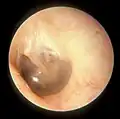

![]() Right eardrum as seen through a speculum | |

When the eardrum is illuminated during a medical examination, a cone of light radiates from the tip of the malleus to the periphery in the anteroinferior quadrant, this is what is known clinically as 5 o'clock.

Right eardrum as seen through a speculum